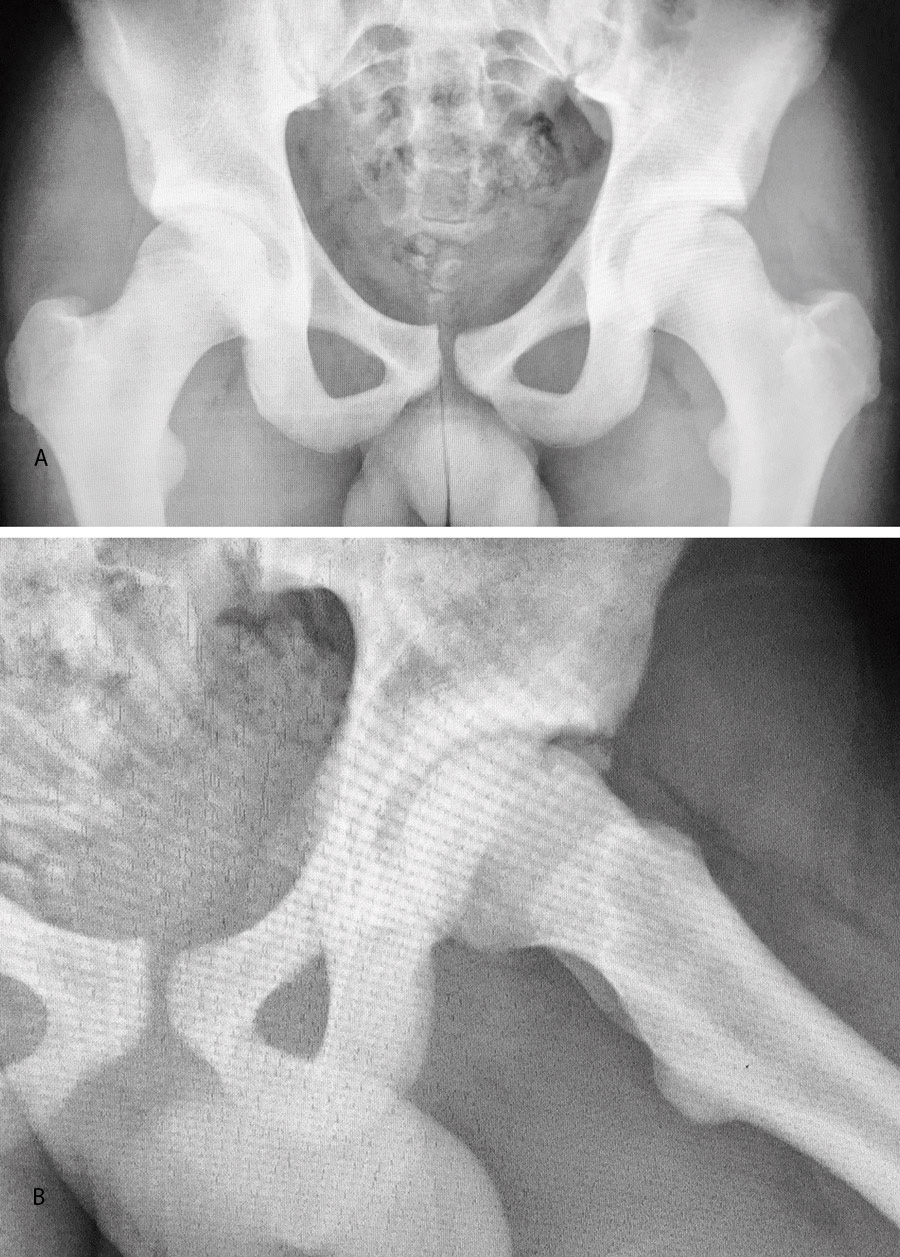

Las pruebas de imagen no muestran alteraciones en forma de deformidad de tipo CAM ni PINCER (tanto en radiografías como en resonancia). El ángulo alfa en la proyección axial era de 38,2° y el ángulo Wiberg de 34,5° (Figura 5). Asimismo, el estudio mediante artrorresonancia no evidenció lesiones de labrum ni deformidades del tipo AFA (Figura 6).